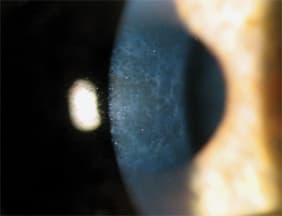

She underwent PRK in both eyes on separate surgery dates one week apart. Unfortunately, she slowly developed sub-epithelial haze (Figure 1) and regression of her myopia in both eyes despite aggressive treatment with topical steroids. An attempt to scrape the sub-epithelial scarring and application of mitomycin in her left eye three years post-operatively failed to reduce the haze. Eight years after PRK her refraction is OD -4.75 DS 20/25 and OS -6.25 DS. The patient was successfully refitted into GP contact lenses (Figure 2) and is satisfied with the vision they provide.

Figure 1